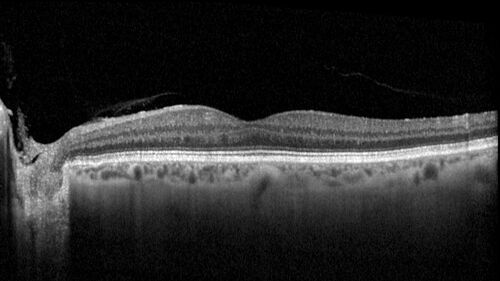

78 year old female with vision loss for 1 week and old macular scar. Images show BRAO with plaques and FA shows occlusion.

BRAO_126199_071725_08.jpg

BRAO and macular scar - plaques in vessel and video